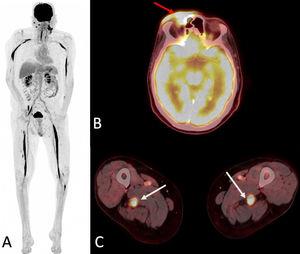

Esta comunicación breve de la Revista Radiología expone la presentación de un linfoma como neurolinfomatosis de los nervios ciático y mediano ¡No te lo pierdas! 🔗 bit.ly/45cmiUi

Esta comunicación breve de la Revista Radiología expone la presentación de un linfoma como neurolinfomatosis de los nervios ciático y mediano

¡No te lo pierdas! 🔗 bit.ly/45cmiUi